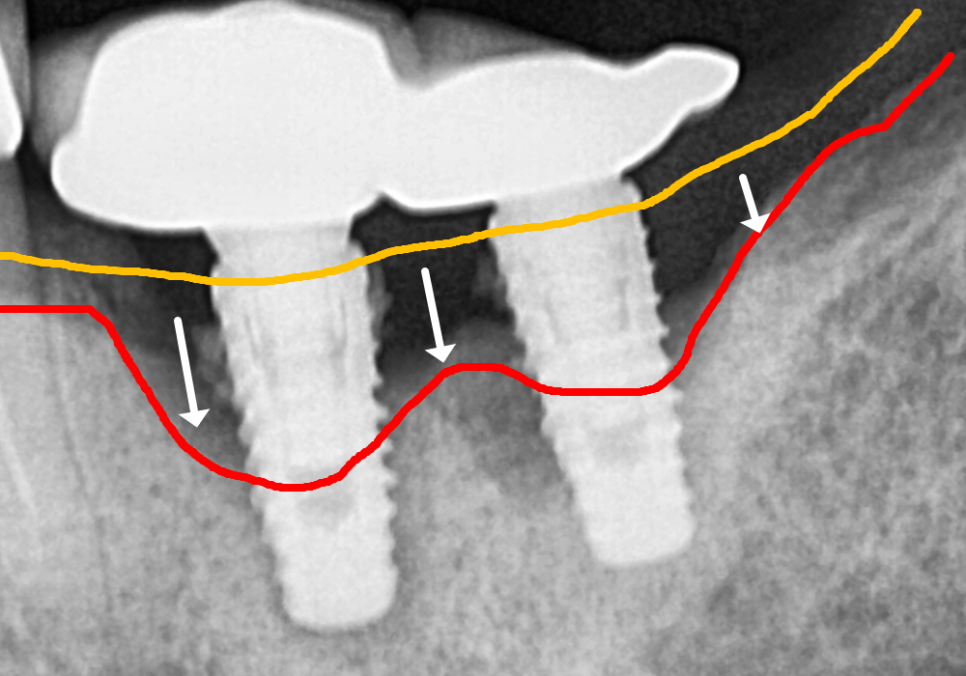

방사선 사진을 살펴보니,

임플란트 주변 뼈가 이미

상당히 소실되어 있는 상태....

CT 상에는 임플란트 뿌리의

약 2/3 정도의 뼈가 녹아,

뿌리 끝부분만 간신히 뼈에 매달려 있는 것을

확인할 수 있었어요.